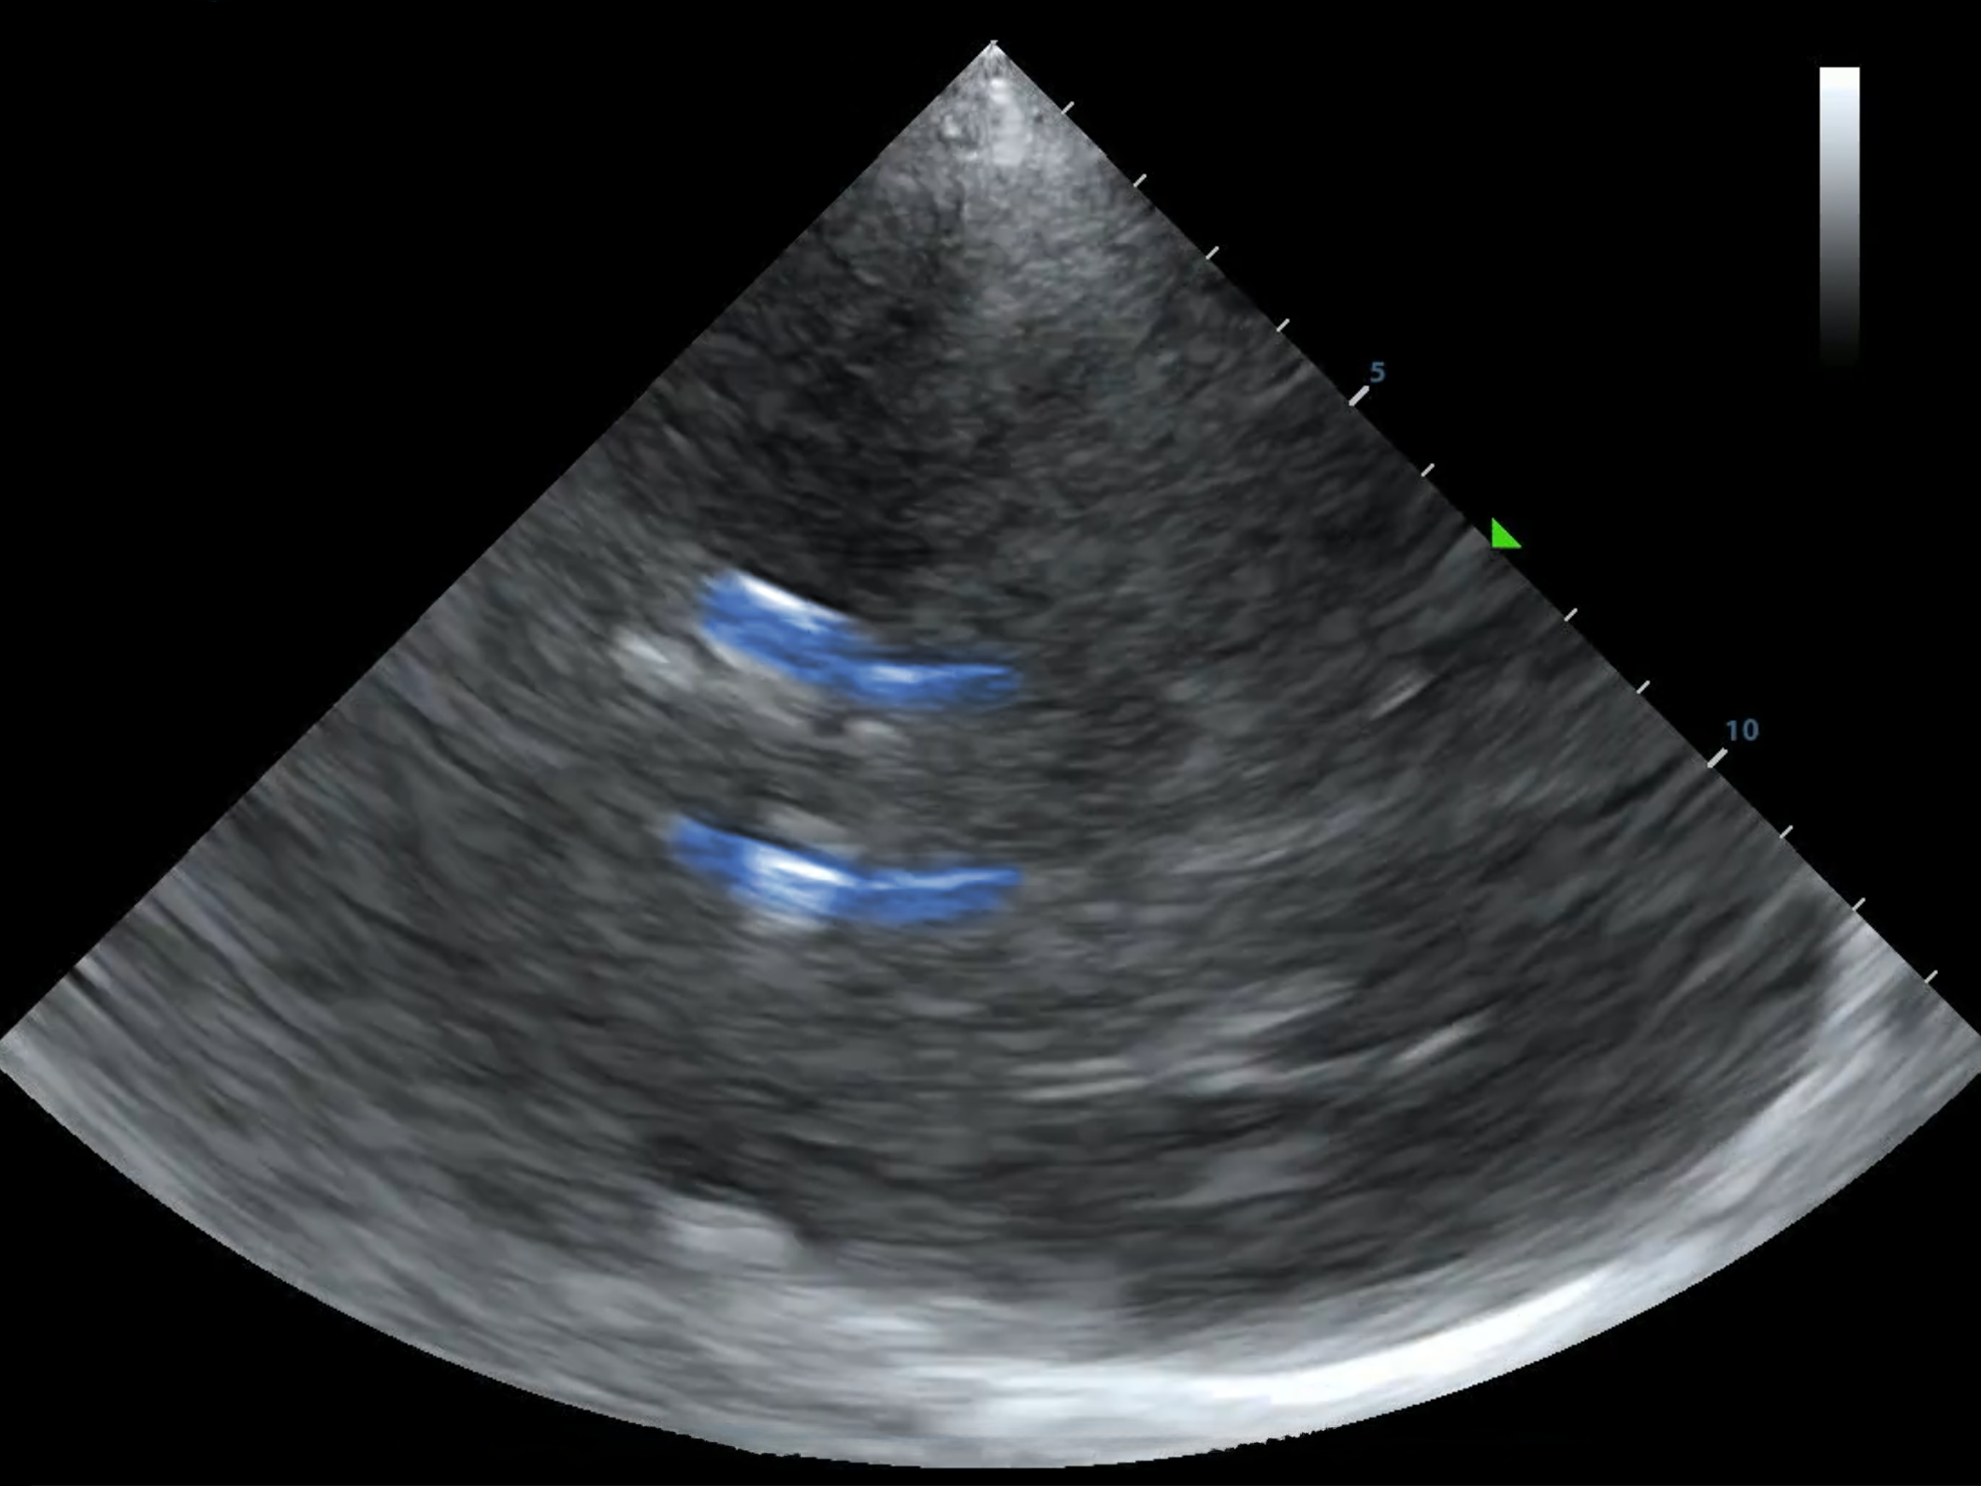

Below, you'll find a normal MCA PI. It's also majestic, virile, ruggedly-handsome, and mine.

As always, I found the MCA with color doppler and put the pulse wave doppler gate on the proximal MCA.

I selected "AutoTrace" and dragged the line from the beginning of the systolic upstroke until end diastole and the machine calculated the rest.

You can also trace the waveform with a cursor, or some machines trace it and provide the calculations without you even asking!